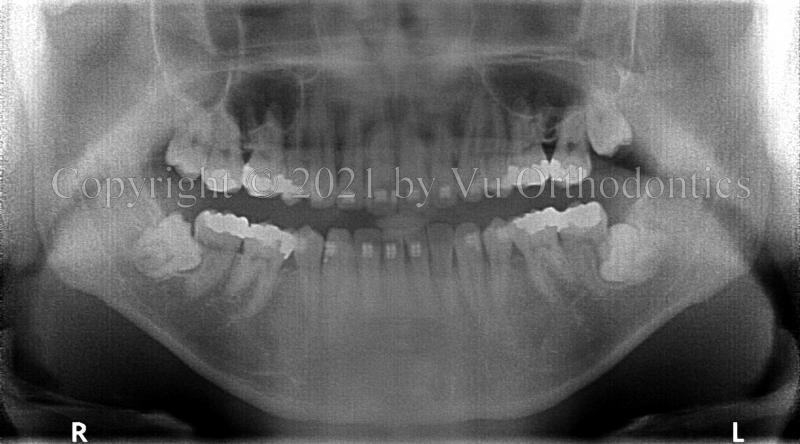

For impacted wisdom teeth, especially on the lower, doing nothing is a bad option. Figure 5 shows the damages to the lower 2nd molars by the corresponding lower wisdom teeth.

(a)

(b)

Fig. 5 Damages to the lower 2nd molars by the wisdom teeth: (a) damaged lower right 2nd molar, (b) damaged lower left 2nd molar.

Another example of damages to the lower 2nd molars by the lower wisdom teeth is shown in Fig. 6.

Fig. 6 Damages to the lower 2nd molars (Teeth #31 & #18) by the wisdom teeth (Teeth #32 & #17): (a) panoramic radiograph, (b) Tooth #31 is the lower right 2nd molar; Tooth #18 is the lower left 2nd molar